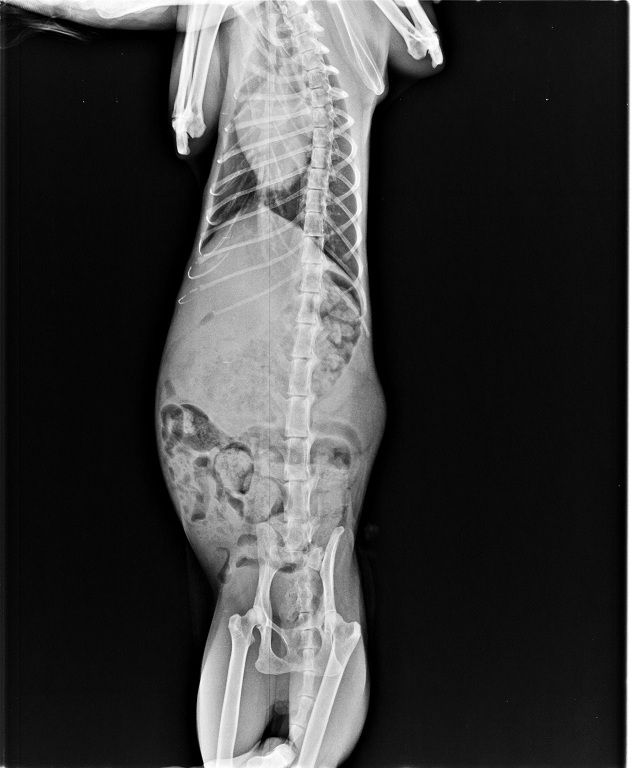

也拍了X光照片,

確認是否有因為跌落水溝傷害到骨頭,

並多檢查了貓愛滋、白血病和心絲蟲等檢測,

所幸各項檢測都呈現陰性反應。